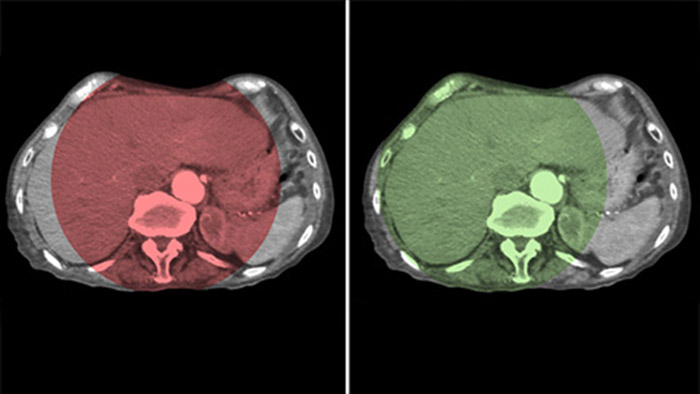

THC Dual permite la adquisición de imágenes en 3D de una fase arterial para visualizar estructuras vasculares y una posarterial (fase retardada) para ver la acumulación del medio de contraste, en un solo paso automático.5

Dual View permite la visualización simultánea de dos conjuntos de datos de la THC. Tanto la fase arterial como la retrasada se pueden mostrar una al lado de la otra o en una sola vista de superposición fusionada.